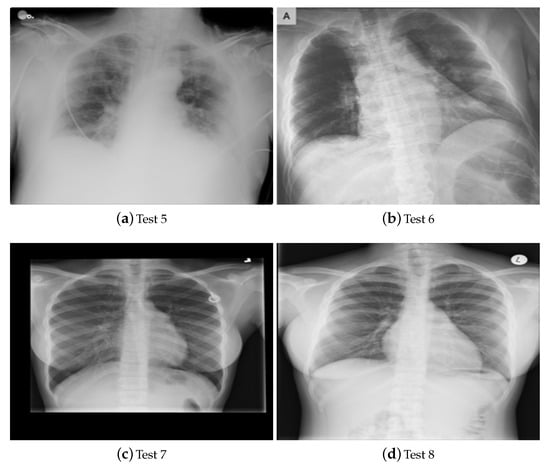

4.1. Benchmark Images